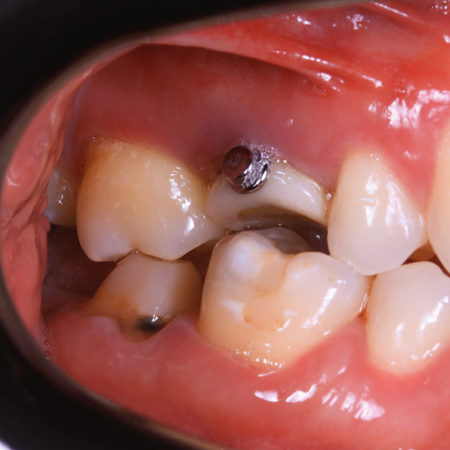

INTRODUÇÃO: O gerenciamento dos espaços das agenesias dentárias é frequentemente relatado como um desafio adicional para o tratamento ortodôntico e, quando associado à má oclusão esquelética, torna o tratamento mais complexo. OBJETIVO: Neste relato de caso, objetivou-se apresentar um tratamento ortopédico seguido de tratamento ortodôntico compensatório de um paciente Classe III esquelética severa com agenesia dentária múltipla. RELATO DE CASO: Paciente do sexo masculino, com 14 anos de idade, teve um plano de tratamento atípico, inicialmente tratado com máscara facial...

INTRODUÇÃO: O gerenciamento dos espaços das agenesias dentárias é frequentemente relatado como um desafio adicional para o tratamento ortodôntico e, quando associado à má oclusão esquelética, torna o tratamento mais complexo. OBJETIVO: Neste relato de caso, objetivou-se apresentar um tratamento ortopédico seguido de tratamento ortodôntico compensatório de um paciente Classe III esquelética severa com agenesia dentária múltipla. RELATO DE CASO: Paciente do sexo masculino, com...

INTRODUCTION: Space management of tooth agenesis is often reported as an additional challenge for orthodontic treatment and, when associated with skeletal malocclusion, makes the treatment more complex. OBJECTIVE: The objective of this case report was to present an orthopedic treatment followed by comprehensive orthodontic treatment of a severe skeletal Class III patient with multiple tooth agenesis. CASE REPORT: A 14-year-old male had an atypical treatment plan, starting with facemask...